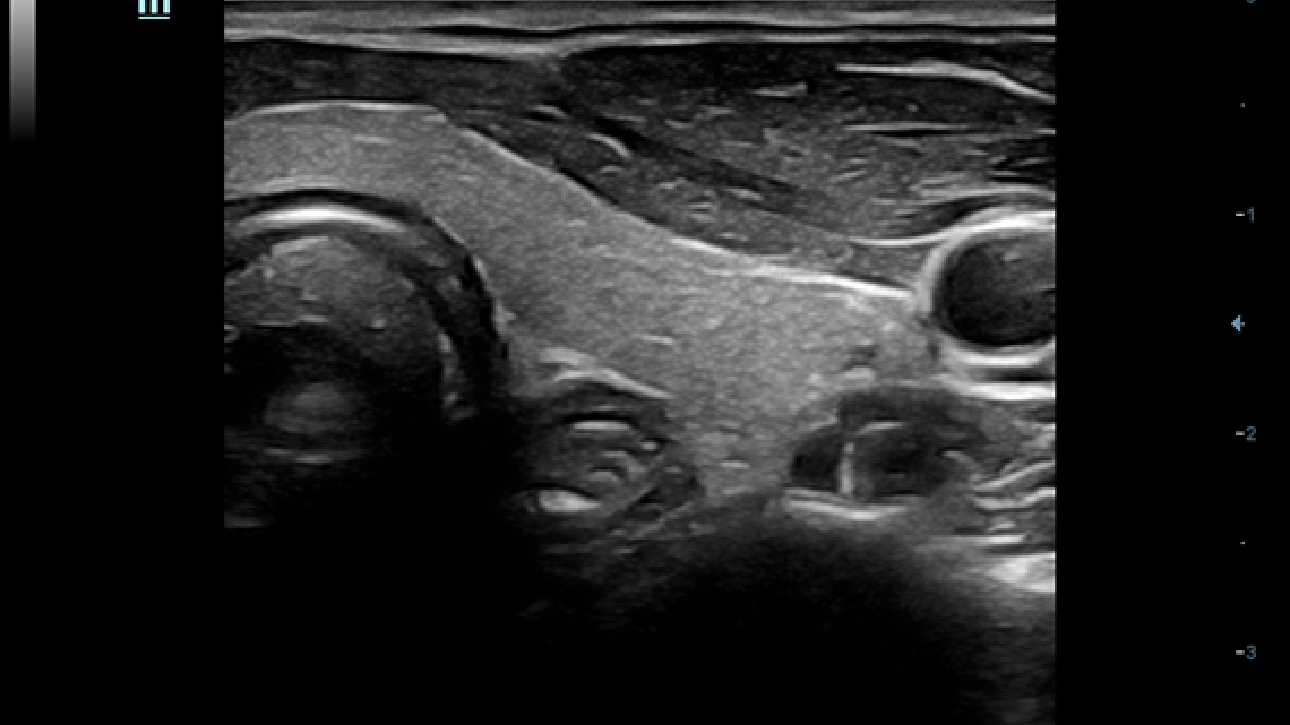

X-Insight is een inzichtelijke oplossing om meer visie te krijgen.

De gloednieuwe oplossing van Mindray is het geslaagde product dat is voortgekomen uit voortdurende klantinzichten in klinische behoeften in combinatie met steeds evoluerende, geavanceerde ultrasoundtechnologie?n. Vol energie en gebrand op toekomstgerichte inzichten en eindeloze mogelijkheden: dankzij de verhoogde schaalbaarheid wordt de oplossing continu verbeterd.

Als allround partner zet DC-60 Exp met X-Insight zich in om een allesomvattende oplossing te zoeken waarmee u alle aspecten van uw dagelijkse klinische activiteiten gemakkelijk en trefzeker kunt beheren.

De DC-60 Exp met X-Insight is ontworpen op basis van diepgaand inzicht in klantbehoeften om hoge effici?ntie met nauwkeurige beeldverwerking te leveren, dankzij eXacte helderheid, eXceptionele intelligentie en eXcellente ervaring.